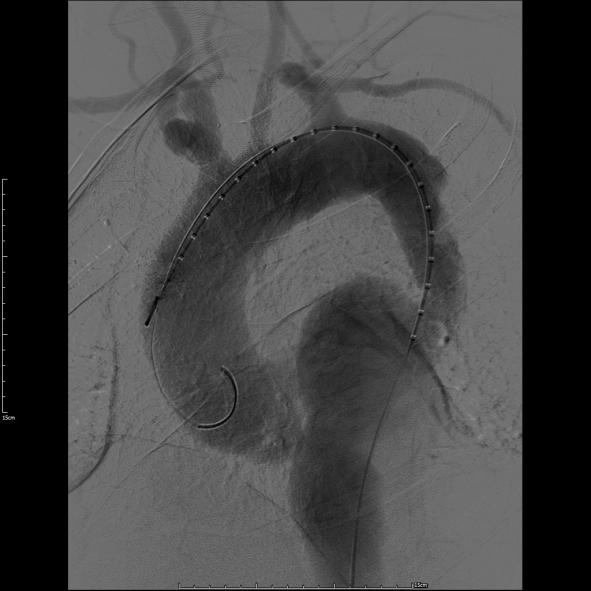

第一例患者确诊为“胸主动脉夹层合并夹层动脉瘤”,病变范围广泛。手术团队创新应用定制化打孔支架技术,术中精准定位并选择性保留重要侧支循环。该技术不仅彻底隔绝了主动脉扩张病变,更通过支架微孔有效维持了截瘫好发区域(T8-L1节段对应脊髓根动脉)的脊髓血供,显著降低了长段覆膜支架覆盖所引发的脊髓缺血及截瘫风险,为弥漫性主动脉疾病治疗提供了更安全有效的解决方案。

第一例患者术前CT

第一例患者术中造影